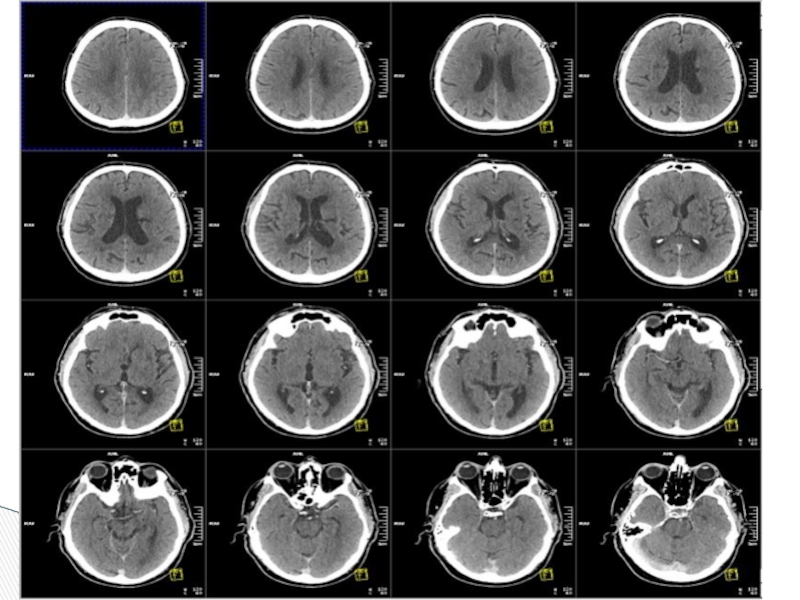

Слайд 3Рентген сәулесіне негізделген ағзаның қабатты (послойный) диагностикалық әдісі.

Компьютерлік томография

Слайд 5Тамыр ( сосудистые) аурулары

Травмалық зақымдану

Ми ісігі

Абцесс

Және т.б жұлын мен бас миының

аурулары

Мына ауруларда ақпаратты әдіс болып табылады.